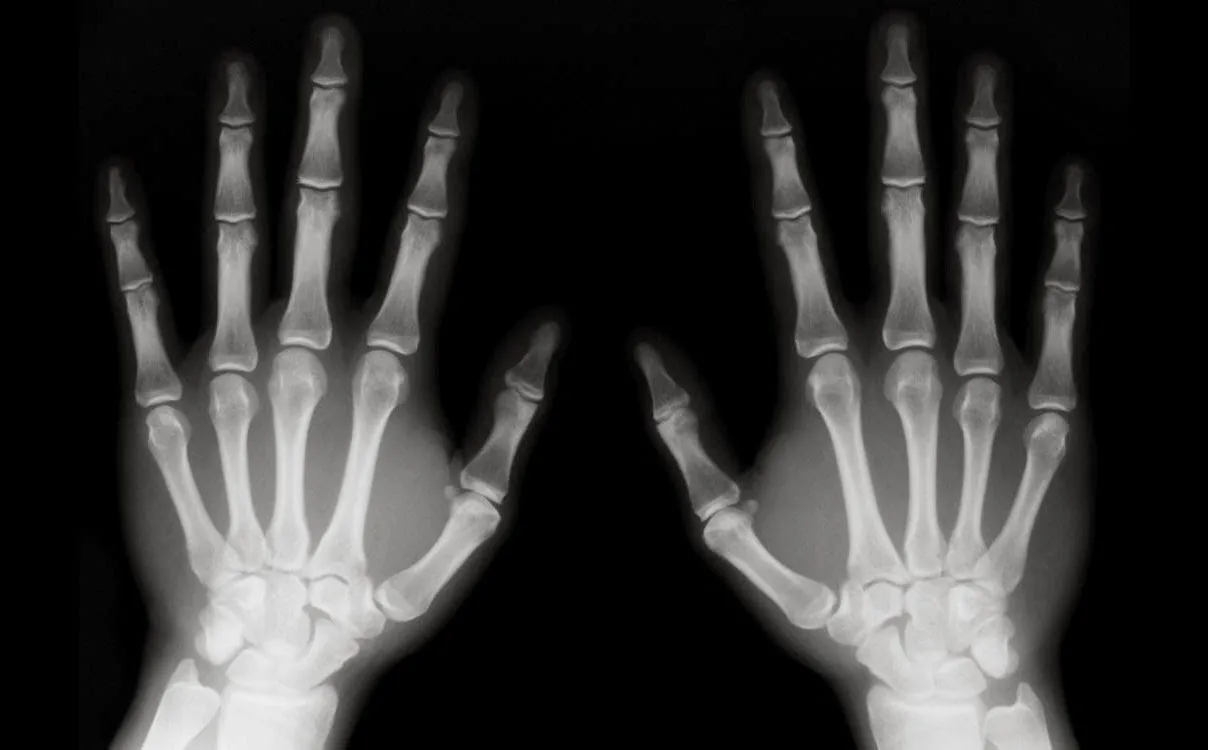

El proyecto, “Sistema basado en Inteligencia Artificial para la detección de osteosarcoma en imágenes de tomografía de fémur”, lo llevó a cabo en el Instituto Nacional de Rehabilitación Luis Guillermo Ibarra (INR) y consistió en desarrollar un software basado en Tecnología Computarizada para apoyar en el diagnóstico de osteosarcoma, el cáncer óseo primario más frecuente en infancias, adolescencias y adultos mayores.

Durante su presentación, explicó que actualmente no existe un caso de estudio o experimento que utilice un dataset de imágenes de fémur obtenidas mediante Tecnología Computarizada para la detección de este tipo de tumor maligno. Su sistema está diseñado para ofrecer apoyo en el diagnóstico en contextos donde no haya un médico especialista disponible, lo que permitiría brindar atención primaria a pacientes en hospitales públicos, considerando la alta carga de trabajo y sobresaturación del personal especializado.

Este desarrollo representa una herramienta de apoyo asistida por computadora, integrando la experiencia médica con el potencial de la inteligencia artificial para mejorar el diagnóstico y tratamiento de enfermedades como los tumores óseos.

La metodología empleada por Emilio incluyó, en un principio, la selección, recuperación y preprocesamiento de imágenes de Tecnología Computarizada, asegurando un balance entre las clases a detectar (tejido sano y tumor), proceso que llevó a cabo en conjunto con radiólogos del INR para asegurar la confianza y precisión de los diagnósticos.